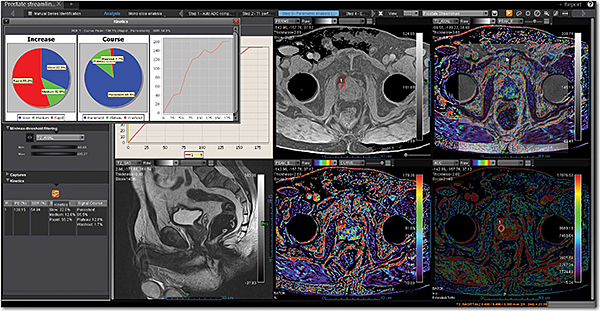

Додаток Prostate Streamlined.

Спеціальні програми Olea SphereTM для аналізу передміхурової залози включають в себе розширені можливості для оцінки дифузії та якісної оцінки перфузії. Також пропонують ефективний мультипараметричний аналіз усіх доступних послідовностей для візуалізації простати. В додатках реалізовано аналіз кінетики та кількісних даних на основі надійних математичних моделей. Програми передміхурової залози включають звіт PI-RADS® 2 для покращення виявлення, характеристики та вірогідності встановлення діагнозу раку простати. Цей програмний пакет стандартизує виклад протоколів опису, а також вказує рівень підозри або ризик виникнення клінічно значущих пухлин.